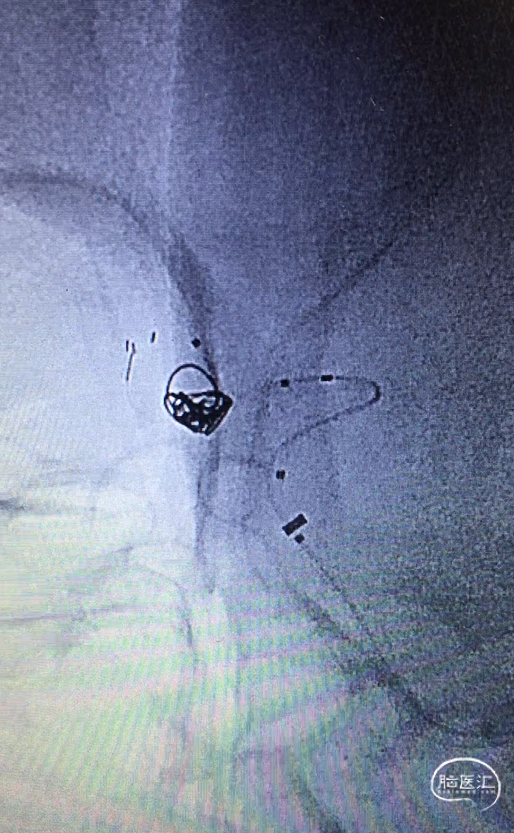

微导管到位

SL-10(直头)置于RACA A2,Atlas支架(直径3.0mm,较血管直径2.0mm大一号)到位,头端在RACA A2(左图);SL-10(头端S型)置于AcoAn左侧分叶(右图)。

支架释放

Atlas支架原位释放,头端打开良好,中部因较血管管腔大,可实现穹隆效果,以保护LACA A2流入道,尾端即将完全释放(左图);Atlas支架继续完全释放,尾端打开良好(右图)。